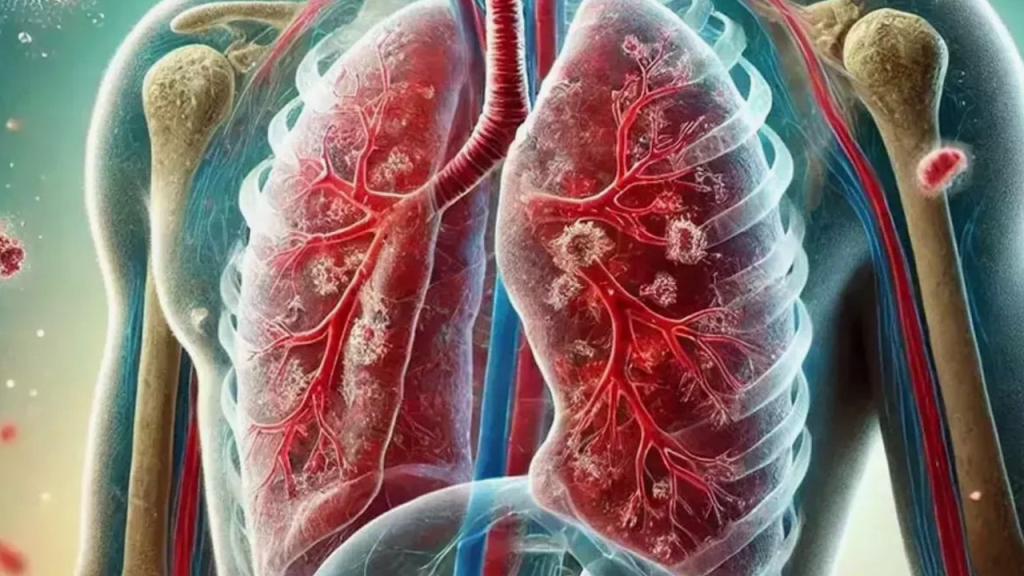

Kluge, ABD merkezli X şirketinin sosyal medya platformundan, tüberküloz hastalığına ilişkin paylaşımda bulundu.

“Tüberküloz, her yıl 1 milyon kişinin ölümüne yol açan dünyanın en ölümcül bulaşıcı hastalığıdır.” ifadesini kullanan Kluge, ilaç direnci, tüberküloz-HIV koenfeksiyonu ve sağlık bakımına eşitsiz erişimin yanı sıra yetersiz finansmanın krizi daha da derinleştirdiğini belirtti.

DSÖ, 12 Kasım’da yayımladığı “2025 Küresel Tüberküloz Raporu”nda, 2024’te 1,2 milyondan fazla kişinin tüberküloz nedeniyle hayatını kaybettiğini ve yaklaşık 10,7 milyon kişinin bu hastalıktan etkilendiğini bildirmişti.